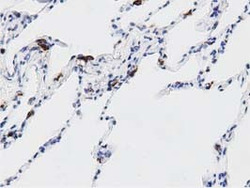

- Experimental details

- Immunohistochemical staining of paraffin-embedded Human lung tissue within the normal limits using anti-DNAJA2 mouse monoclonal antibody. (Heat-induced epitope retrieval by 10mM citric buffer, pH6.0, 100C for 10min, TA501710, Dilution 1:50)

- Validation comment

- IHC